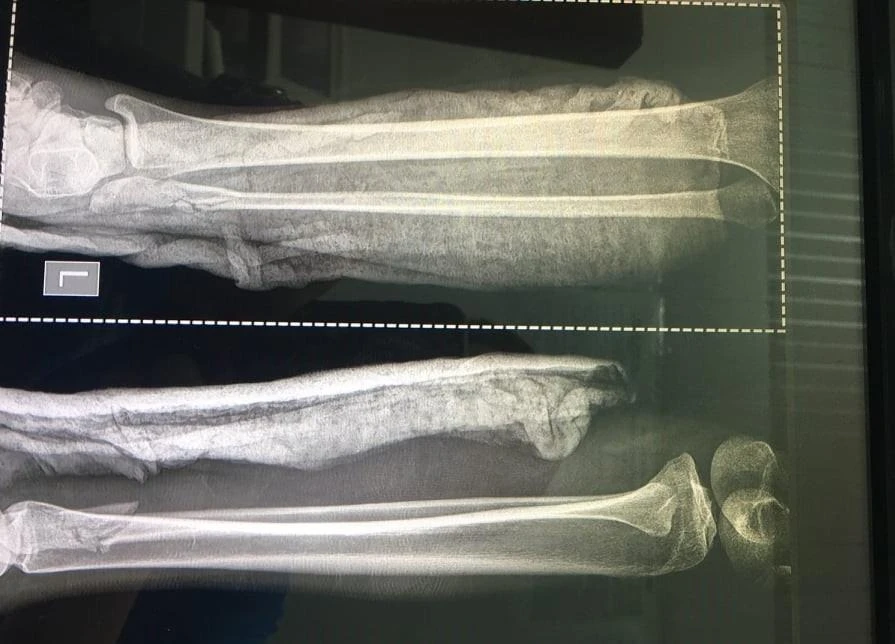

Theo BV Chợ Rẫy, bệnh nhân bị chấn thương đầu, vỡ nền sọ (gãy xoang sàng hai bên); cả tay trái và phải bị gãy xương trụ, xương quay, xương mác; gãy nhiều xương ngón tay ở bàn tay trái… Đặc biệt nạn nhân đang có thai sống khoảng 26 tuần.

Cả tay và chân nạn nhân đều bị gãy.